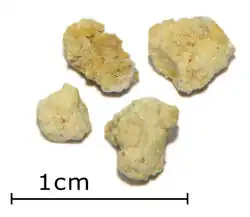

Die Bildung von Speichelsteinen wird als Sialolithiasis bezeichnet. Meistens tritt sie in der Unterkieferspeicheldrüse (Glandula submandibularis) auf (80 %), in selteneren Fällen (ca. 20 %) kann sie auch die Ohrspeicheldrüse (Glandula parotidea) betreffen. Speichelsteine sind eine recht häufige Erkrankung (etwa 27 bis 56 von einer Million Einwohnern), die Männer und Frauen gleich häufig betrifft. Ursache ist meistens eine gestörte Sekretion (Dyschylie), etwa eine Änderung der Zusammensetzung des Speichels. Die Steine bestehen meistens aus Calciumphosphat. Klinisch machen sie sich meistens durch Schwellung und Schmerzen der betroffenen Drüse vor allem beim Essen bemerkbar. Die Steine können je nach Lage und Größe chirurgisch entfernt werden, neuerdings werden auch Ultraschalltherapien therapeutisch eingesetzt, die die Steine zerkleinern und einen natürlichen Abgang durch das Kanalsystem ermöglichen. Bei der sogenannten Speichelgangsendoskopie (auch Sialendoskopie) können kleine Steine unter direkter Sicht mit Zängelchen oder Körbchen entfernt werden.